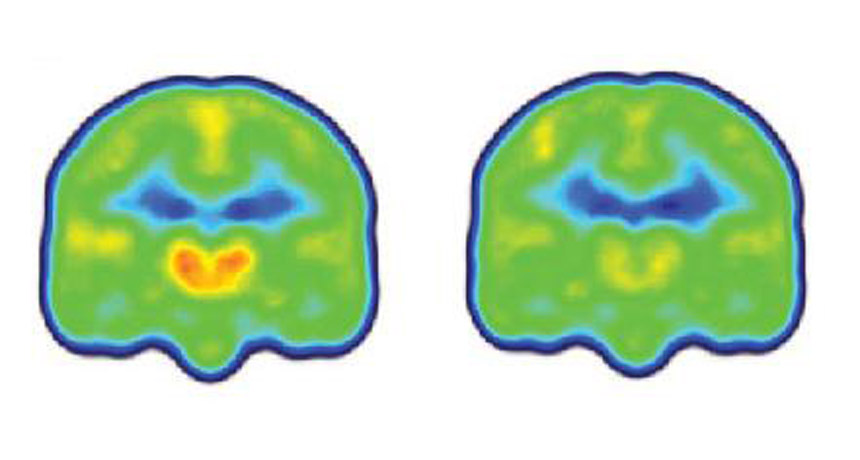

SEEING PAIN  People with chronic pain (left) have higher levels of a protein linked with inflammation (orange and red) in their brains than people without chronic pain (right), a finding that could help improve treatments for the condition.

MARCO LOGGIA, MASSACHUSETTS GENERAL HOSPITAL